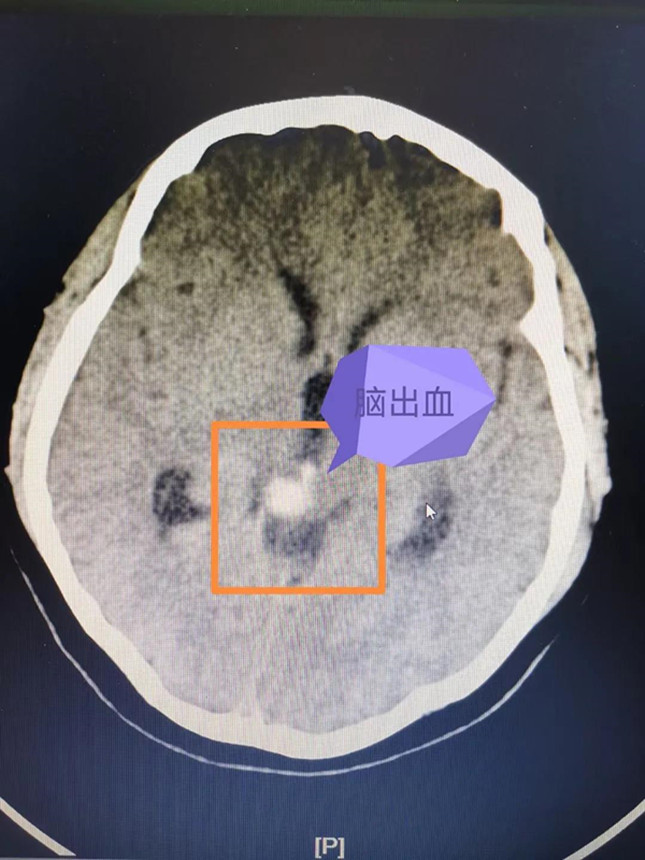

经过头颅CT检查,接诊的巴特尔副主任医师发现大梅存在着非常危险的脑干出血,对于没有高血压病史的年轻患者,他立即想到了脑血管疾病的可能性,于是很快进行了头颅MR检查,发现脑干出血周边有可疑的异常脑血管影,初步确定了之前的推测。

但是脑血管疾病种类较多,形态多样,头颅MR仍然无法进一步确诊,诊断脑血管疾病的“金标准”则是全脑血管造影(DSA),海西州人民医院此前已经具备了此项特殊检查的硬件设施和人员配备。巴特尔副主任医师更是在2年前就在浙大一院进修学习掌握了全脑血管造影技术。于是,他随后即带领海西州人民医院的本土团队为大梅顺利开展了全脑血管造影术,术中发现大梅的小脑幕区贴近脑干处,有个直径约1cm、像蚯蚓一样扭曲的脑血管畸形。

脑血管畸形是一种先天性的脑血管疾病,脑出血是脑血管疾病最常见的发病表现。已经有过出血的脑血管畸形随时有再次破裂的风险。而核桃大小的脑干是生命中枢,掌管着人体的呼吸、心跳、体温等最基础的功能。脑干出血属于脑出血中最危险的一种,通常情况下,哪怕是2~3毫升的脑干出血都可能引起严重后果,一旦出血量超过5毫升,死亡率高达70%以上。大梅的生命危在旦夕,却又无法长途转运。而且脑干周围的脑血管畸形的治疗极其复杂,风险极高,如何成功“拆弹”、挽救患者的性命,巴特尔医生心里没底。